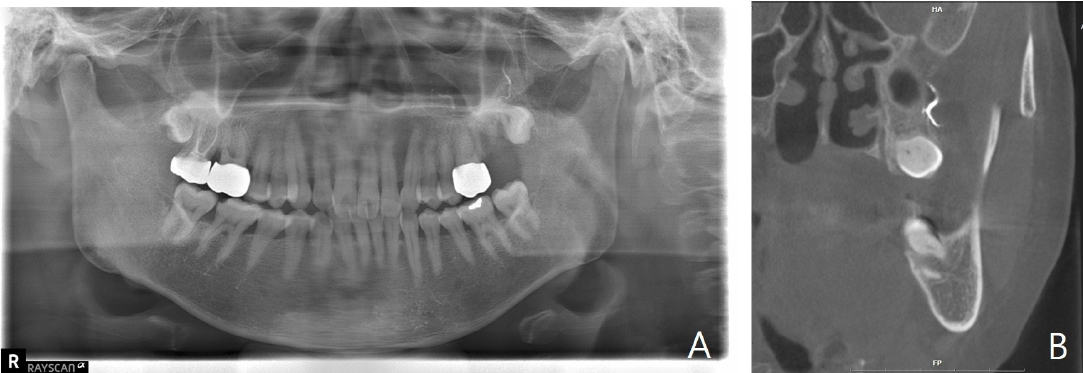

Panoramic view, periapical view and enhanced computed tomography (CT) scan were performed to evaluate the condition further, revealing the extrusion of calcium hydroxide paste over the root apex (Figs. 2A and B). Facial angio CT performed upon presentation to the emergency department showed opacification loss in the branches of the left maxillary artery and skin loss with depression in the left buccal area, without evidence of a fistula tract or subcutaneous inflammation, indicating a possible vascular cause. Based on the findings from the enhanced CT scan, the patient was diagnosed with Nicolau syndrome (Figs. 2C and D).

Radiographic examination performed at the initial examination. A and B. Periapical and panoramic views show extrusion of calcium hydroxide paste beyond the root apex of the left maxillary second molar (arrows). C and D. Facial angio computed tomography demonstrate loss of contrast in the posterior superior alveolar artery, indicating arterial obstruction (arrows).

A. Panoramic radiograph taken approximately six weeks after the incident shows persistent radiopaque material in the periapical region, consistent with extruded calcium hydroxide. B. Coronal cone-beam computed tomogrpahic image demonstrates the presence of extruded calcium hydroxide within the adjacent soft tissue space.